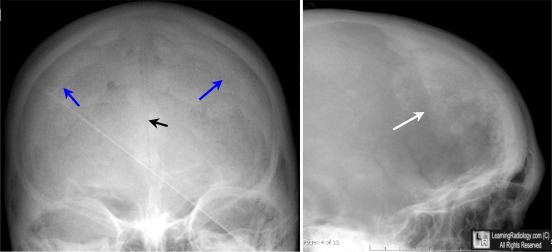

Ну, и "картиночки" для аппетиту...

Экзофтальм на стороне гиперостоза

Костные разрастания на внутренней костной пластинке лобной кости слева

Из наблюдения Елены Юрьевны

Женщина , 1967 г.р.Жалобы на головную боль,головокружение, утомляемость,слабость.На краниограммах -гиперостоз внутренней пластики лобной кости или ... я уже стала придираться ко всему ?Не знаю.

А что с ней?) Нормальная вроде кость. Пахионки, невыраженный неравномерный гиперостоз.

Ни остеолитических, ни остеосклеротических очагов.